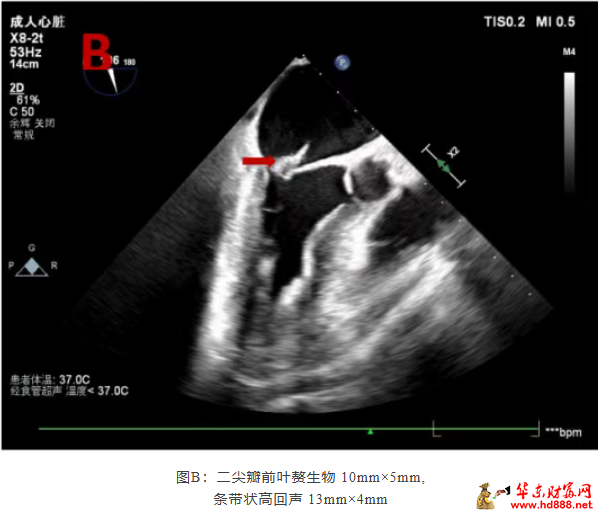

术中所见触目惊心:二尖瓣前叶可见大小约 10mm×5mm 赘生物,后叶腱索断裂并穿孔;主动脉瓣无冠窦可见 5.6mm×5mm 赘生物,左冠瓣亦多处穿孔,心脏瓣膜结构被严重破坏,与术前经食道超声探查结果高度一致!

条带状高回声 13mm×4mm